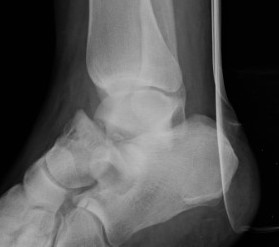

Xrays

| AP | Lateral | Canale View |

|---|---|---|

| Entry point of the screws |

Evaluate neck reduction

|

Evaluates the neck reduction |

Lateral off articular surface Medial through articular cartilage |

Depth of screws |

Beam angled 75o to foot Foot 15o pronated |